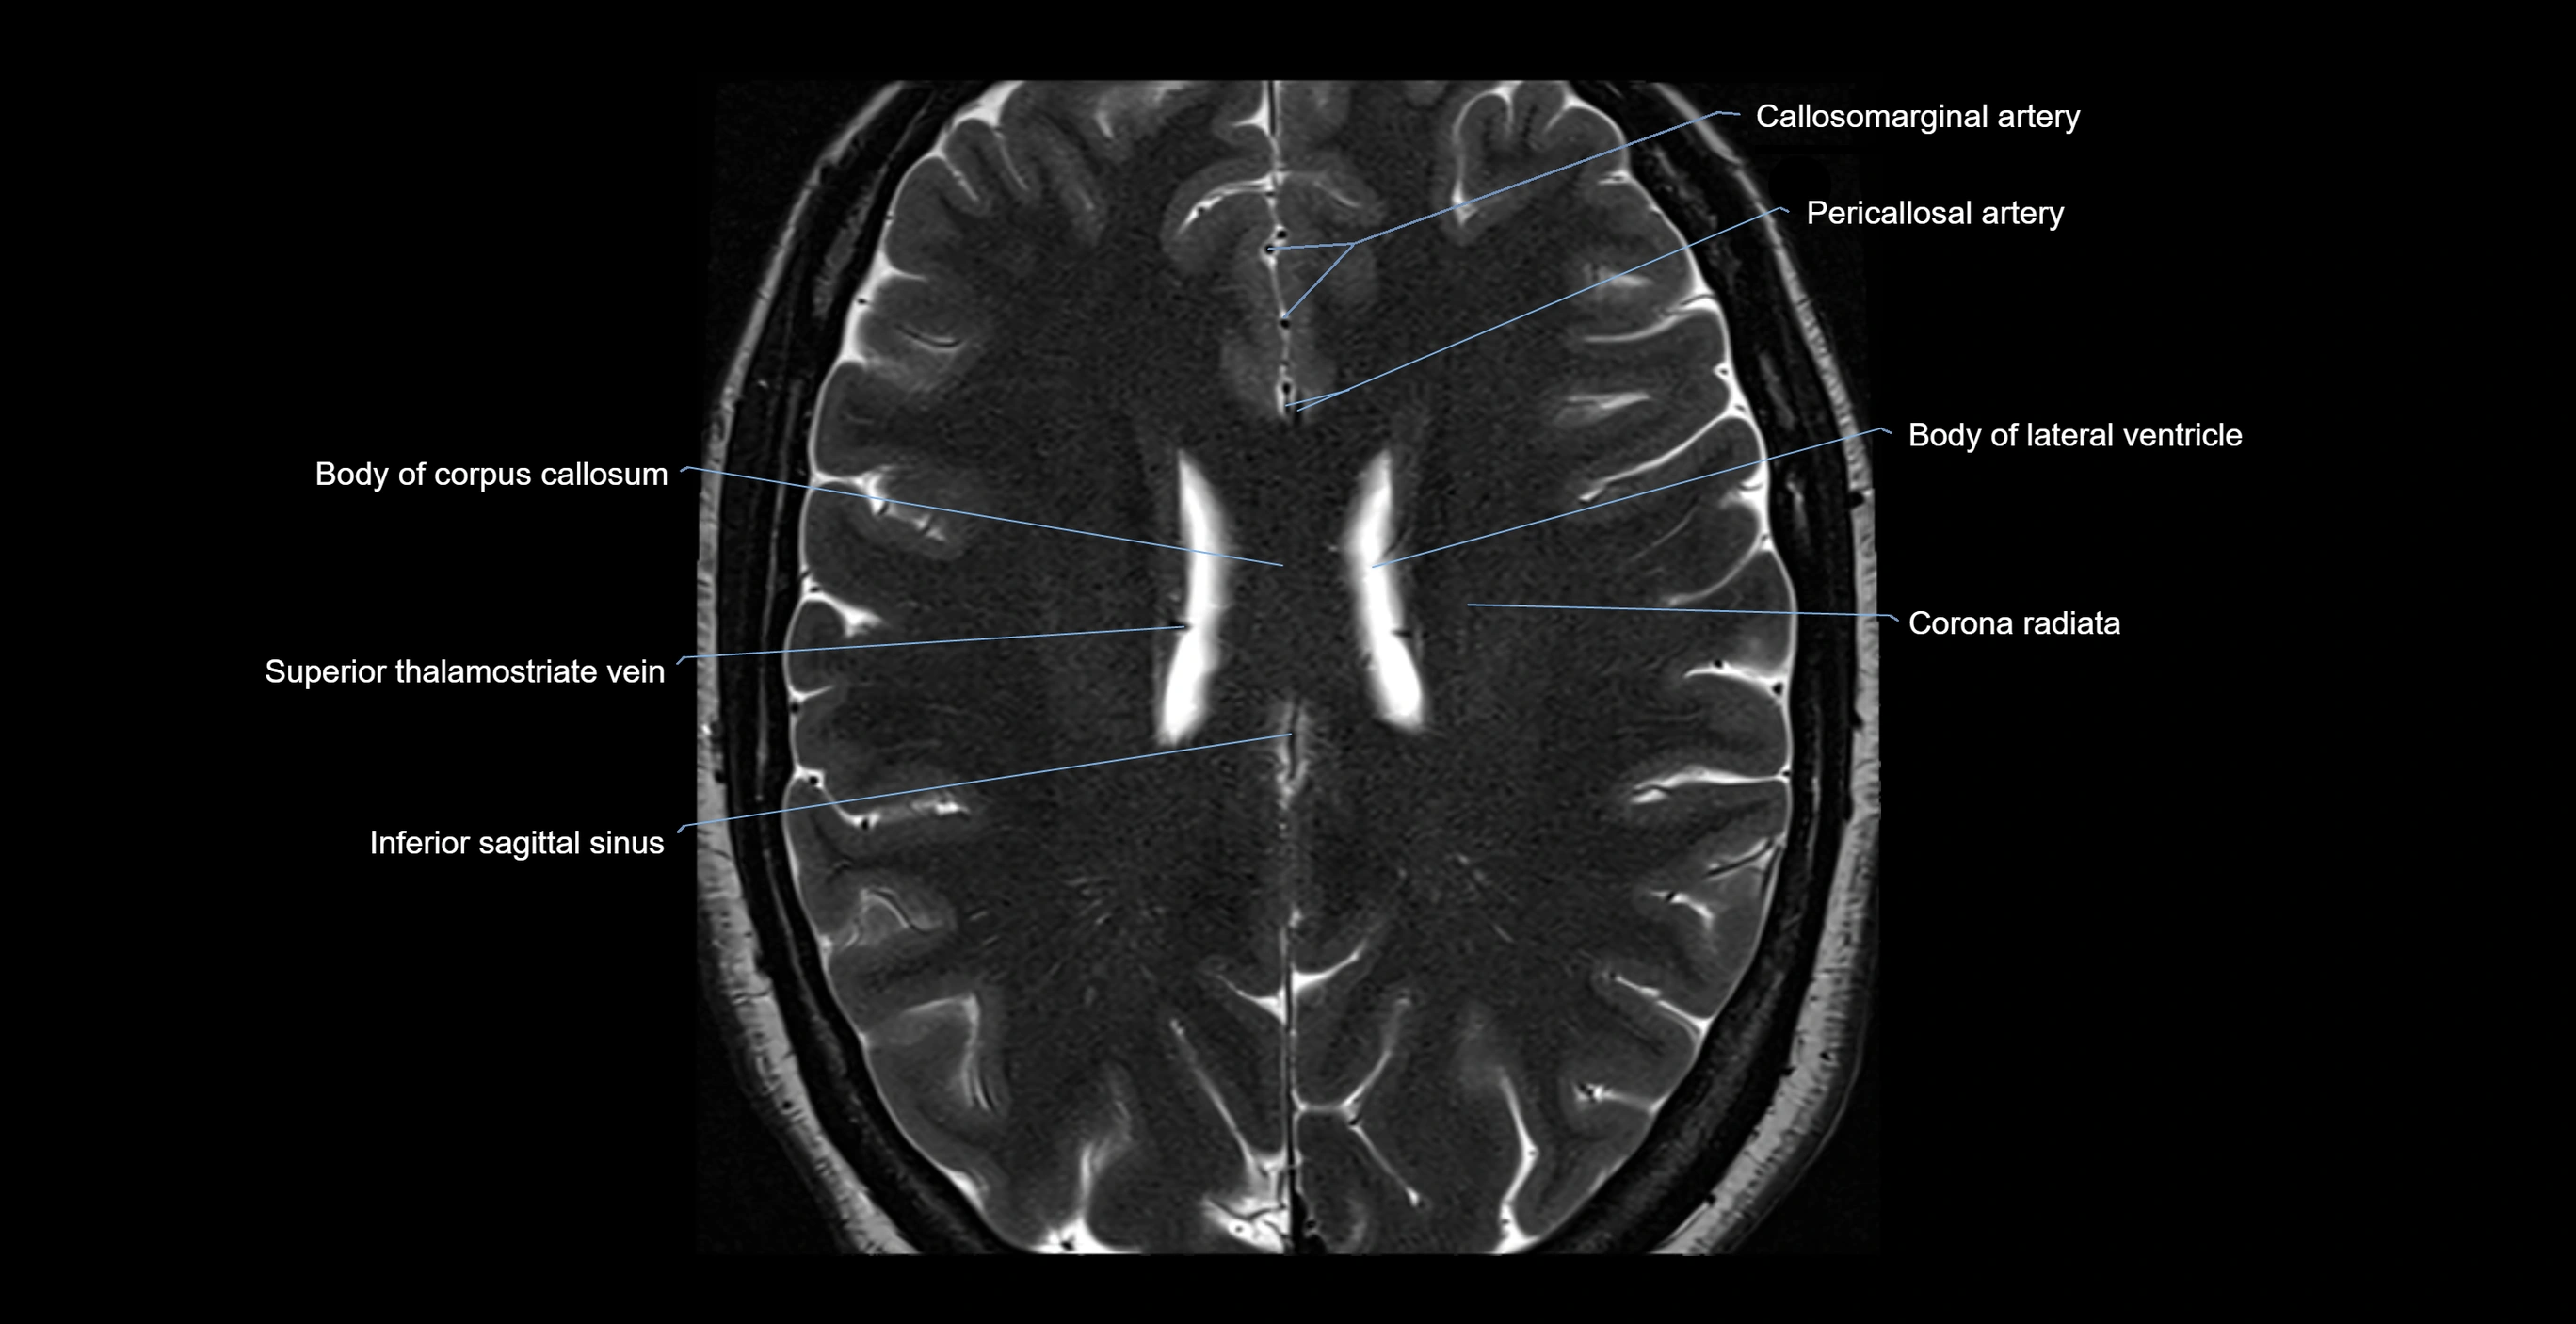

MRI images